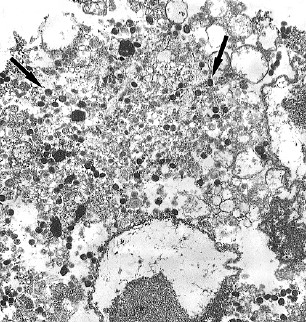

Materials and methods. Clinical isolates of Escherichia coli, Klebsiella pneumoniae, and Pseudomonas aeruginosa species were obtained from 4 patients with recurrent UTI. Cytotoxicity analysis was performed on HeLa cells using the CytoTox 96 kit. Bacterial flagellar motility was assessed in 0.25% agar by measuring the zone of motility. Biofilms were cultivated in 96-well plates and stained with crystal violet and Congo red. Biofilm structure was assessed by microscopy, and the bacterial biofilm and exopolysaccharide matrix were quantified by measuring the optical density of the dye bound to the biofilm. Intracellular development was studied in PC-3 cells by determining the number of intracellular bacteria using a cell lysate plating method and an immunochemical method involving staining the bacteria with specific antibodies.

Results. The Fluorothiazinone antibacterial specifically inhibited the cytotoxicity and motility of E. coli and P. aeruginosa. For K. pneumoniae, susceptibility to Fluorothiazinone was observed, associated with the suppression of cytotoxicity. For all the isolates studied, inhibition of biofilm formation on an abiotic surface was demonstrated. For E. coli and K. pneumoniae, a significant decrease in intracellular replication within human prostate adenocarcinoma cells and suppression of intracellular bacterial community formation were observed.

Conclusion. Fluorothiazinone disrupts mechanisms that contribute to pathogen persistence in the formation of chronic UTI, including biofilm formation on abiotic surfaces such as catheters, stents, and drains, and the formation of intracellular bacterial communities and dormant intracellular reservoirs.